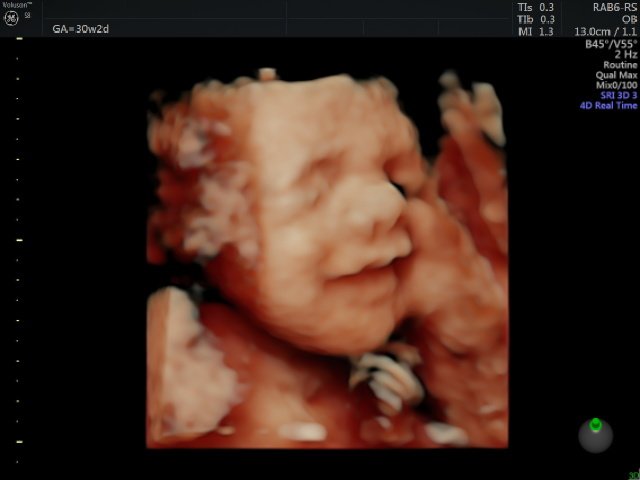

About Expectancy Scanning Studios Ltd Award winning 5* women's health ultrasound services in Kent offering 2D ultrasound in Fertility & Gynaecology & 3D 4D pregnancy scans. Also offering NIPT/Harmony Test and Group B Strep (GBS) Test (not currently routinely offered on NHS). We are the only baby scan and gynaecology/fertility scanning service in Kent led by a qualified Midwife, offering a personal service and with longer appointment ti... (Show more)